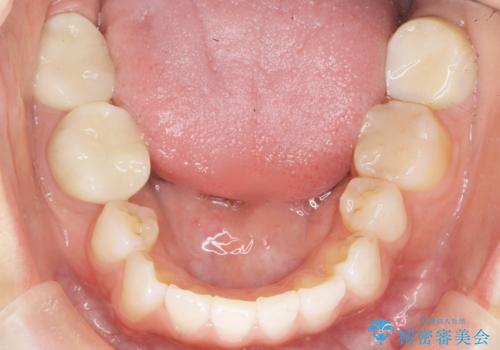

矯正せずに隙間を閉じることができ、ご満足頂けました。

セラミッククラウンの審美的な仕上がりと咬み心地に喜んで下さいました。

クラウンの種類:オールセラミッククラウン スタンダード